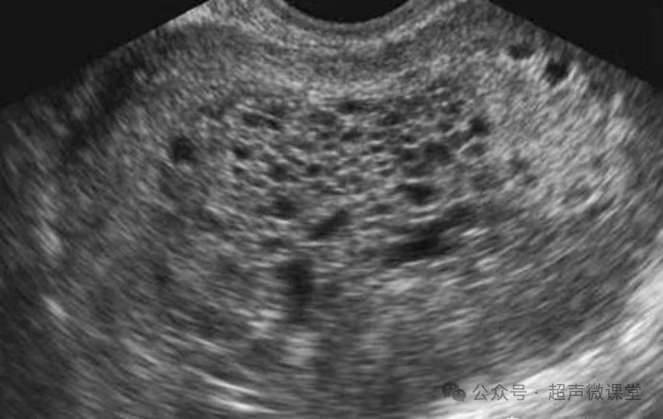

转移性肝癌

葡萄胎